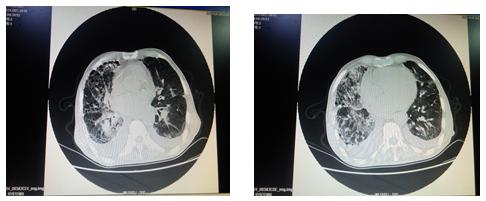

胸部CT:1.两肺间质性病变、间质纤维化可能;2.两侧胸腔积液,两侧胸膜肥厚粘连;3.肺门区及纵膈淋巴结增大,局部钙化;4.主动脉迂曲,主动脉壁钙化,心脏饱满;5.心包积液可能;6.考虑肝顶部钙化燥或胆管结石可能;7.所示胸部骨质改变,结合病史,考虑转移瘤可能。

以下是病人入院胸部CT: